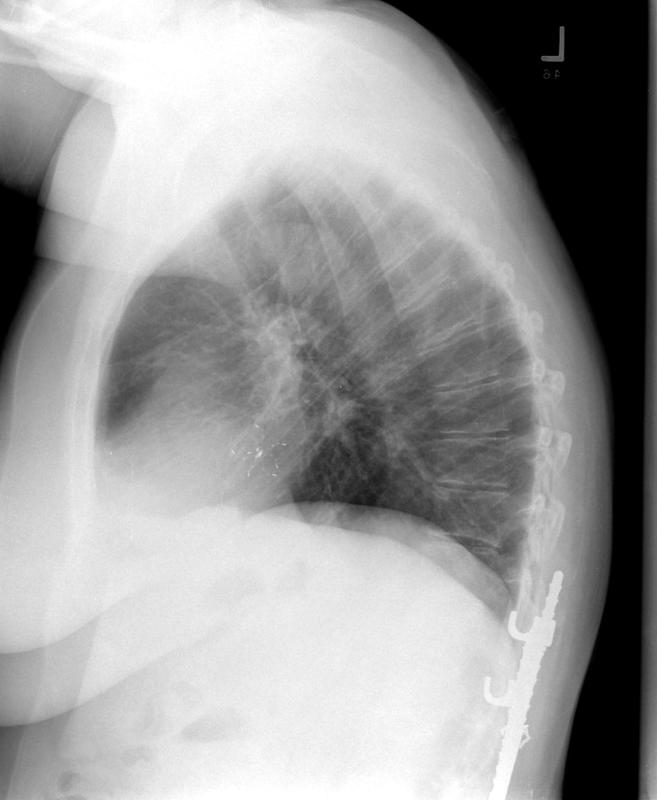

Cardiac

Cong Ht Disease

clamshell 1